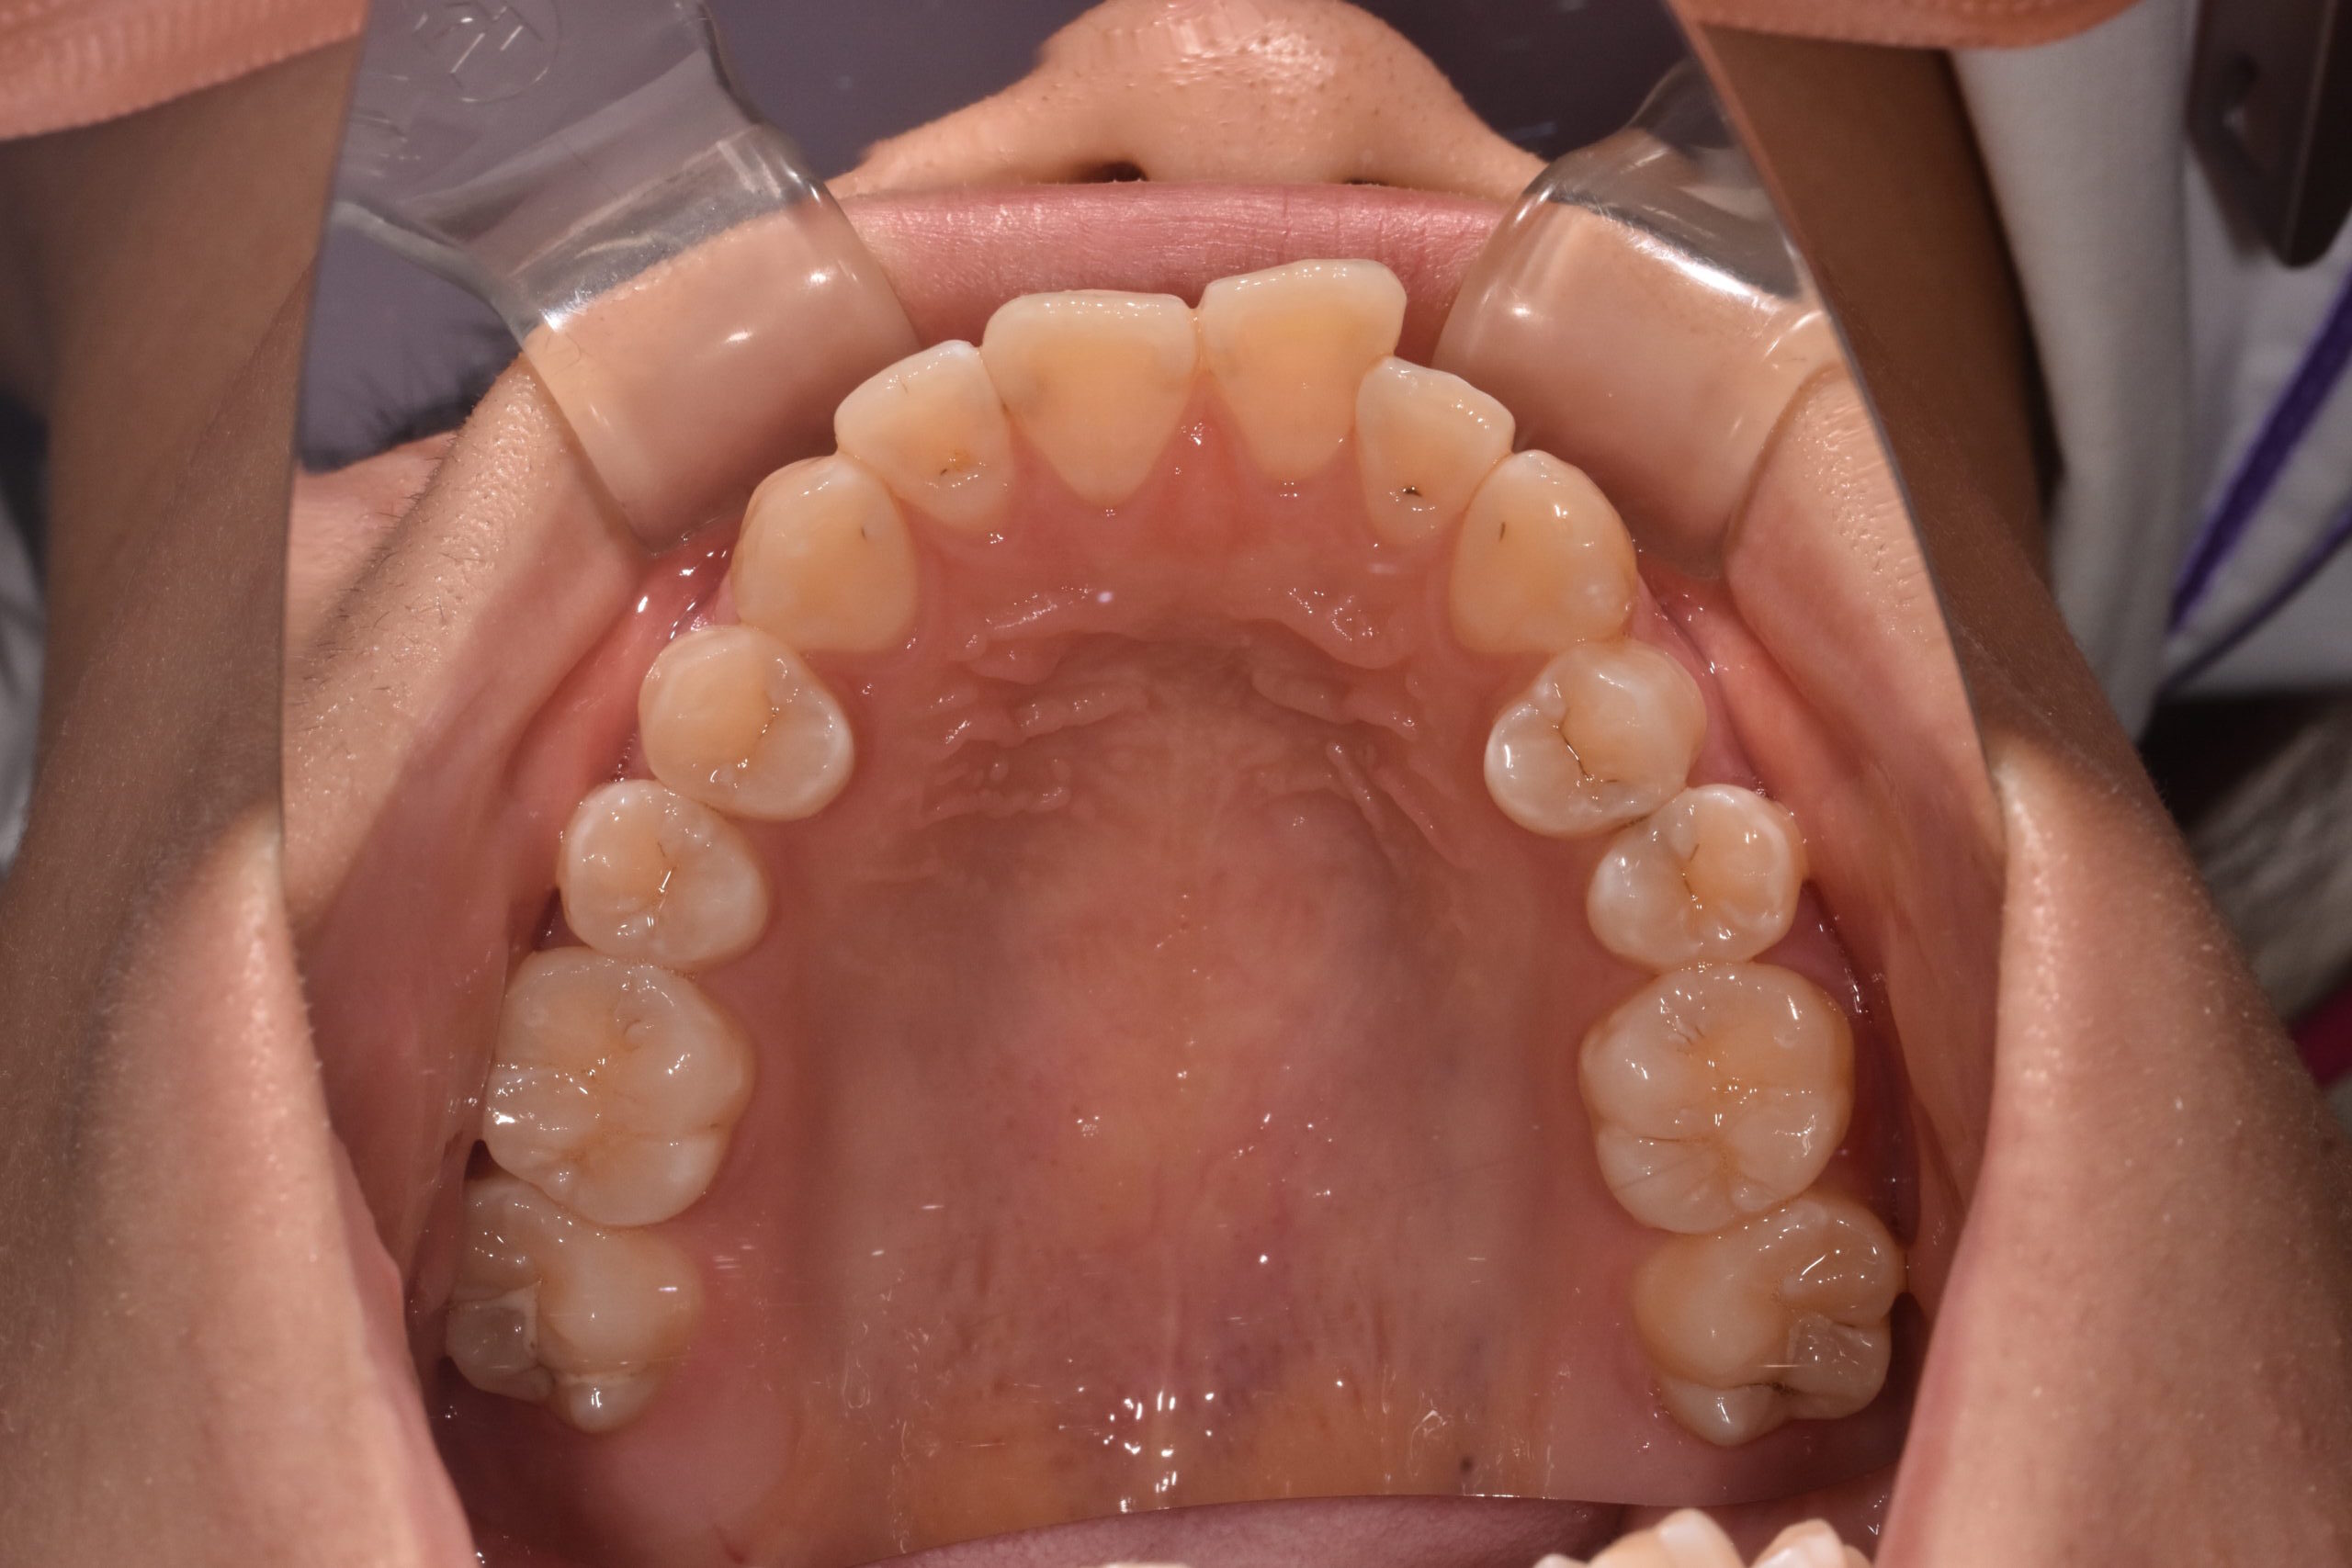

開咬 17歳 女性

治療前

骨格:開咬傾向(前歯が噛みにくいタイプ)

歯並び:前歯が噛み合わない(開咬)+前歯の突出傾向

上下左右の第1小臼歯(4番)を抜歯し、マウスピース型矯正装置を用いて歯並びとかみ合わせの改善を行いました

・抜歯によりスペースを確保し、前歯の位置と角度をコントロール

・奥歯の高さを調整し、前歯がしっかり噛むように改善